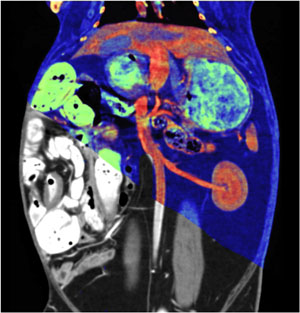

"With DECT, structures with different atomic make-up, such as iodine, calcium and dense blood or metal, are vividly differentiated," said Dr. Yeh at the RSNA 2019 Annual meeting. "Even when objects have identical HU on a regular CT, with DECT different materials appear like different colors."

The benefits of these different colors, aka "color vision," makes DECT a transformative technology in daily clinical practice. Dr. Yeh explains that radiologists routinely encounter ambiguous lesions at CT in their daily practice. Since many types of materials may have similar HU values, it is hard to tell whether a lesion is enhancing, calcified or hemorrhagic. DECT shows radiologists what the underlying atoms are and readily differentiates among such entities.